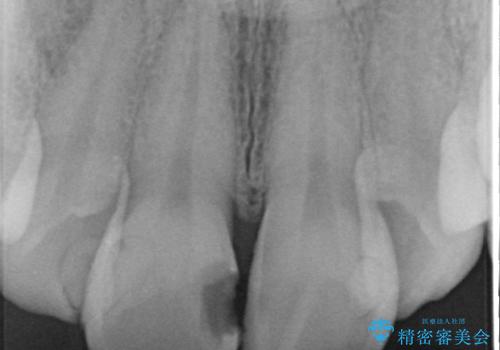

- 上顎前歯の見た目が気になるのでセラミックにしたいといらっしゃった方の症例です。

右上2は歯の神経が死んでおり、根尖病変を認めたため根管治療を行いました。

その後右上1,2番目及び左上1番目の歯に対してオールセラミッククラウンによる補綴を行いました。